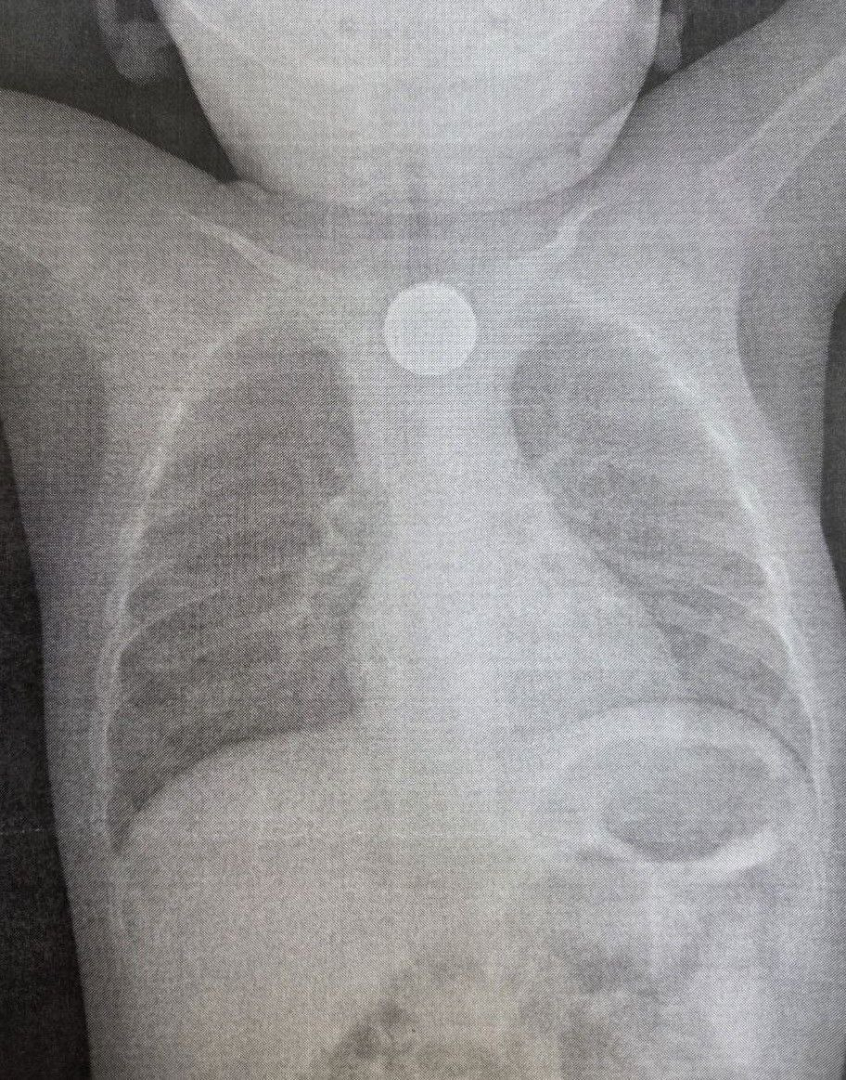

В Бурятии годовалый ребенок получил ожог пищевода 3 степени, проглотив дисковую литиевую батарейку и двухрублевую монету. Малыша спасли врачи ДРКБ.

Медики в составе врача-эндоскописта Зорика Хангалова, эндоскопической медицинской сестры Ларисы Никитиной и анестезиолога-реаниматолога Романа Цвикевича оперативно удалили монету и литиевую батарейку из пищевода при помощи внутрипросветной эндоскопии. Последний предмет вызвал химический ожог слизистой оболочки пищевода 3 степени, представляющий серьезную угрозу для жизни ребенка.